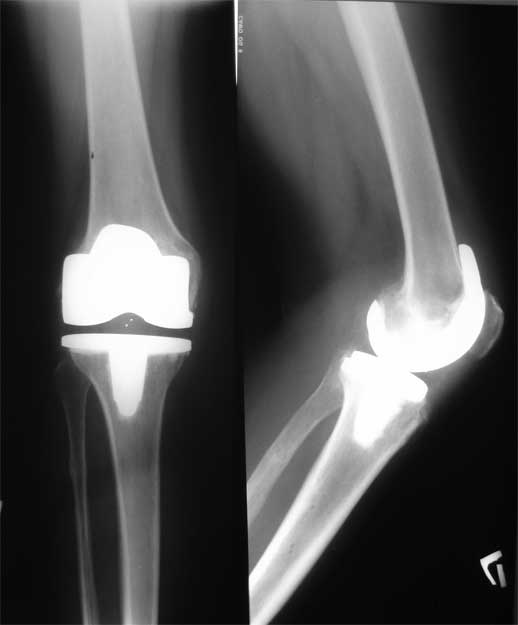

Уважаемые коллеги, пациентка 45 лет около 9 мес назад была прооперирована по поводу правостороннего коксартроза э/п LCS Complete RP.

послеоперационный период без особенностей, объем движений в 6 мес с/р - 110/0/0. Через 9 мес после операции возник напряженный гемартроз (без травмы, перегрузок), получено до 190 мл свежей крови, далее фиксация в ортезе, повторные пункции. через 2 нед выписана из стационара без признаков гемартроза. Через 2 нед аналогичная ситуация. Вопросы :причина? как лечить?